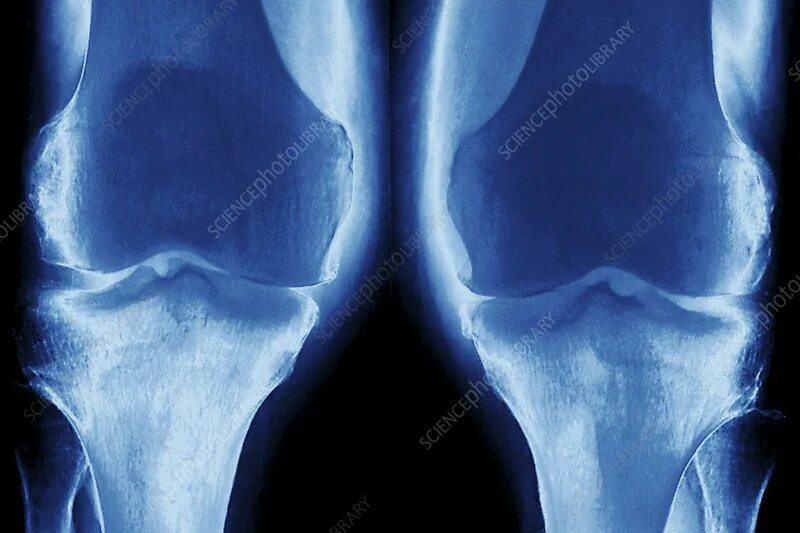

Явления остеоартроза